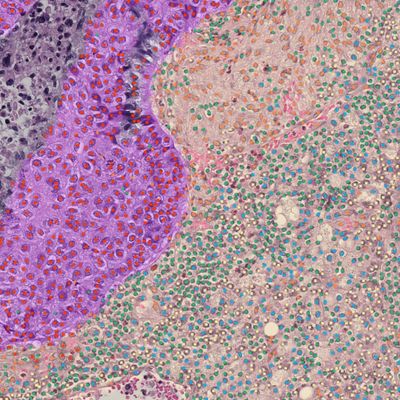

Drive biomarker and drug discovery by unlocking novel insights on disease pathophysiology, biomarker expression, and drug response at the tissue and cellular level.

- AI spatial analyses for H&E and IHC signatures and predictions.